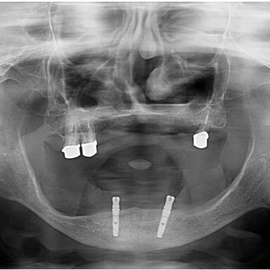

Pacjentka lat 72, od kilkudziesięciu lat chorująca na cukrzyce I typu, obecnie od 10 lat na pompie insulinowej. Profesor medycyny, siostrzenica pacjentki prowadzi swoją ciocię diabetologicznie, pacjentka świadoma zagrożeń przy zabiegach regeneracji kości i implantacji w takim ogólnym stanie zdrowia. Po rekonstrukcji tkanek miękkich i kości osadzono dwa implanty o średnicy 5,0 mm. Na zdjęciu śródzabiegowym widać zadowalające wyniki rekonstrukcji tkanki kostnej. Po upływie kilku miesięcy wykonano nadbudowę protetyczną.